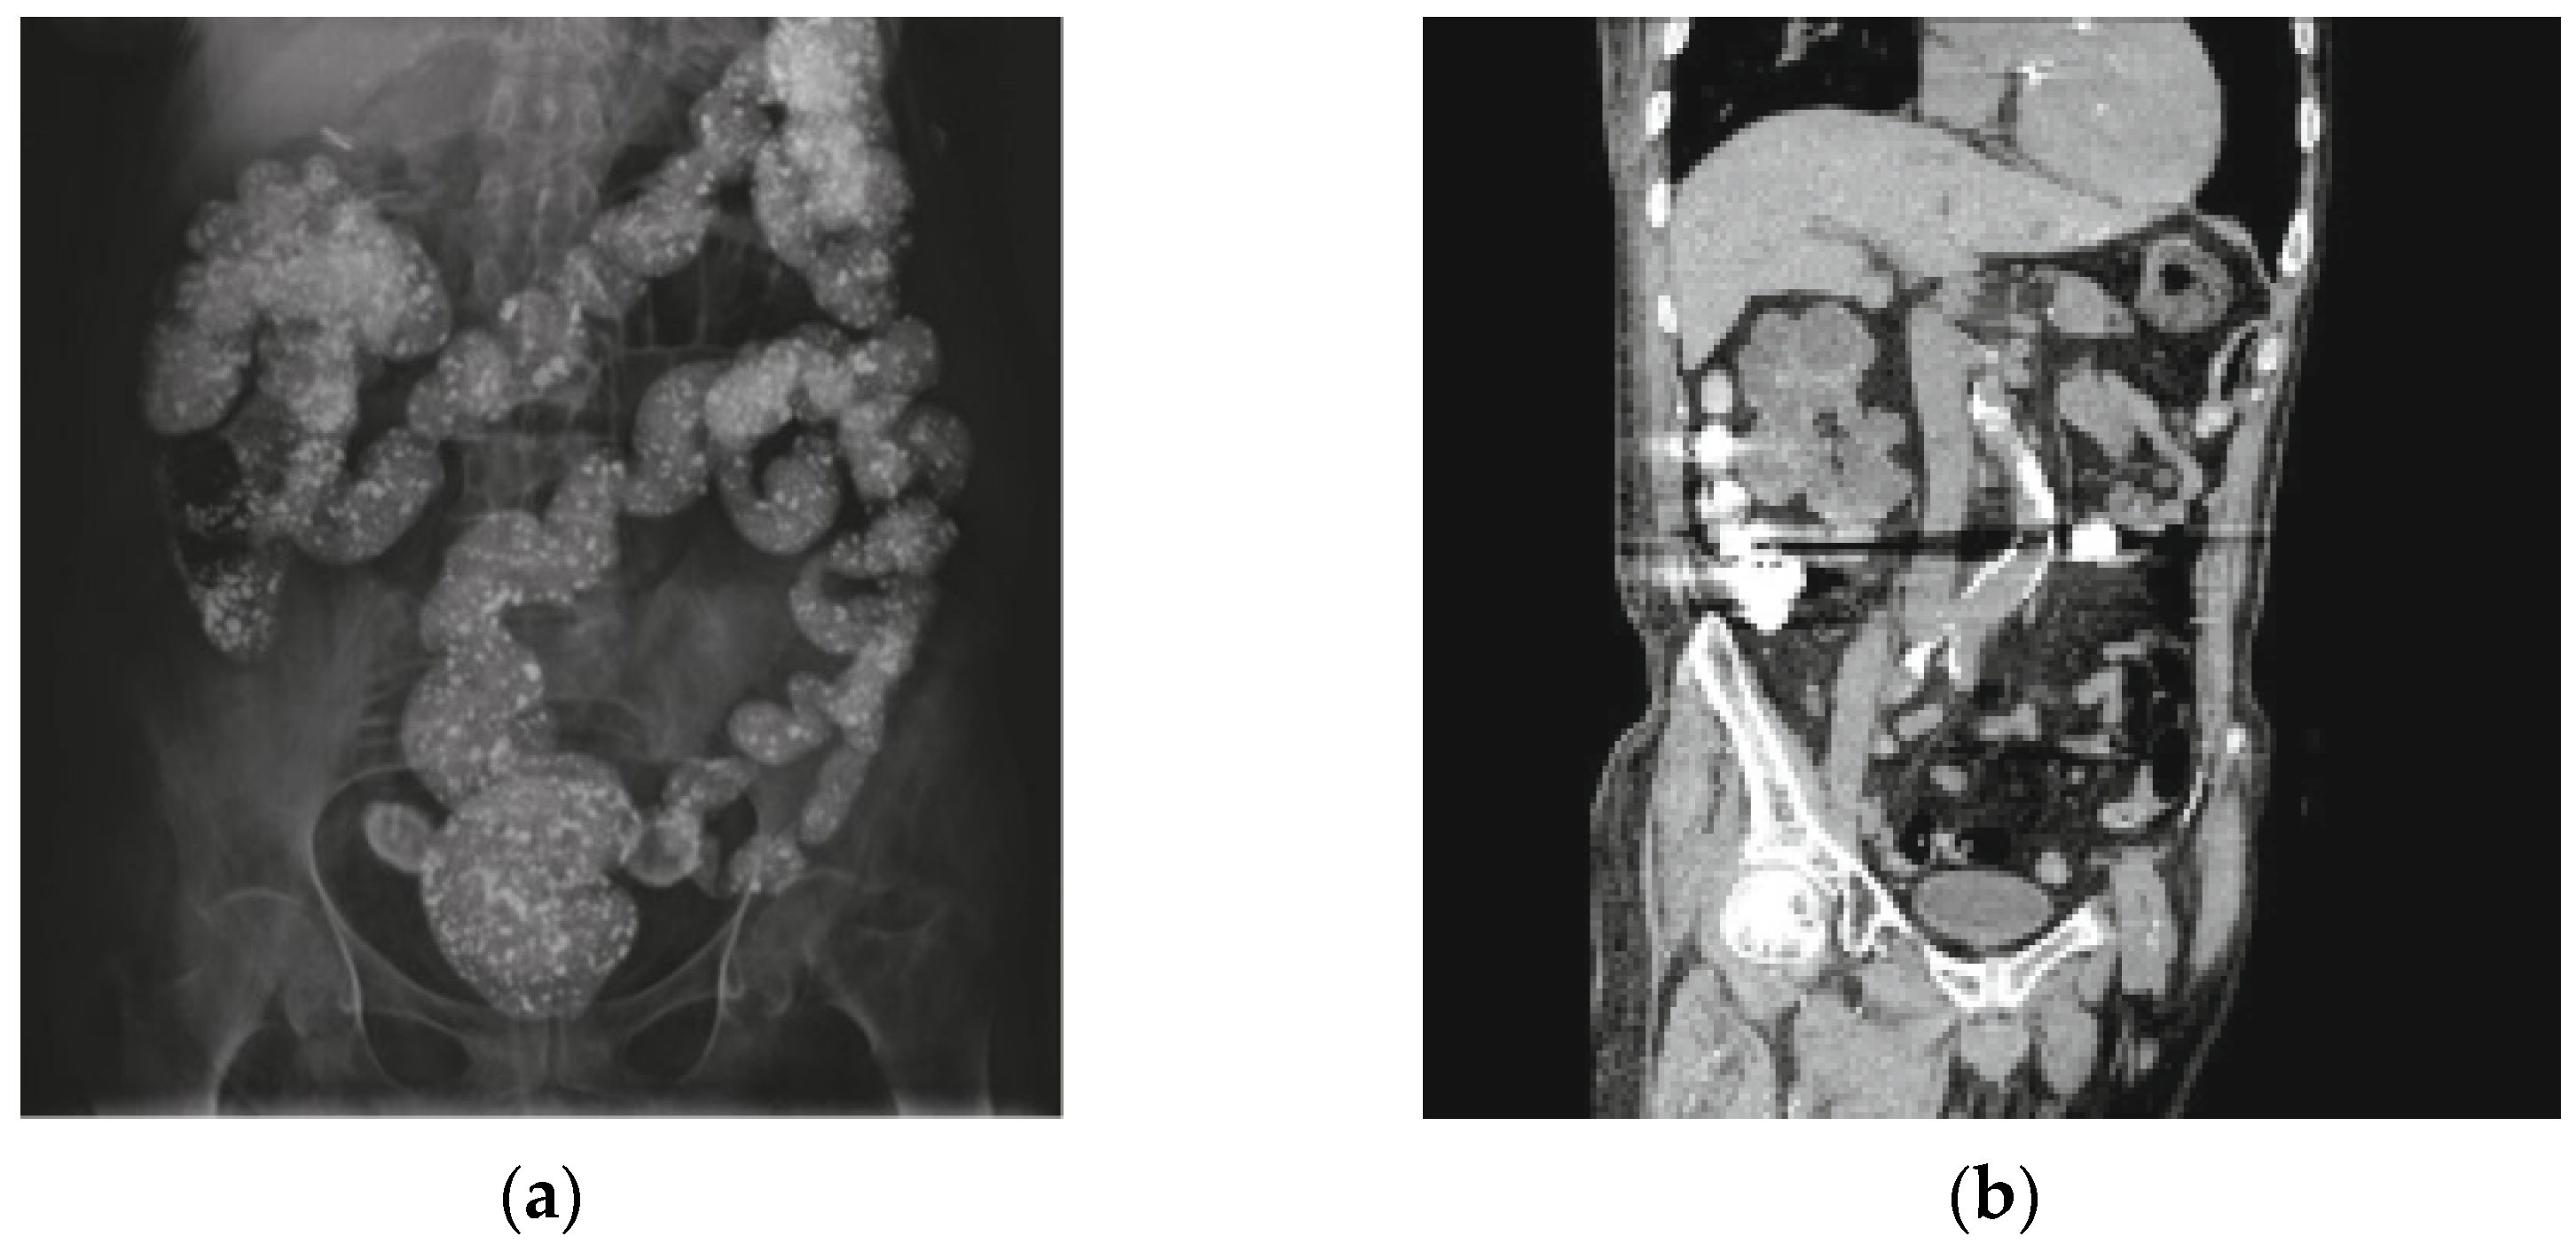

| Chang et al. | 2018 | X-ray + CT | Multiple, scattered radiopaque densities. | Colon | Barium contrast | Clinicians may take its radiopaque characteristic as an advantage to assess the patient’s drug adherence. | Starry-sky bowels|SpringerLink |